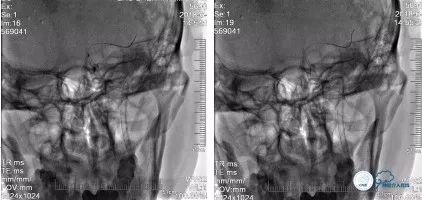

再次经球囊Guiding导管动脉推入4ml替罗非班。遂再次沿Transend微导丝送入自膨式 Enterprise(4.5mm*28mm)支架,准确定位后缓慢释放,再次手推造影提示支架贴壁欠佳,再次以同样方式送入Tazuna球囊(2.5*20mm)扩张支架后,造影提示:左颈内动脉管壁较前改善,前向血流较前改善(TICI分级2b级),无急性血管闭塞征象(图21)

术后患者无不适主诉,血压130/80mmHg,心率72次/分,神经系统查体较前无明显变化,术后即刻行头CT检查未见出血(图21),安返病房。

术后头颅CT(2018-06-14):左侧半卵圆中心散在陈旧性梗死灶(图22)